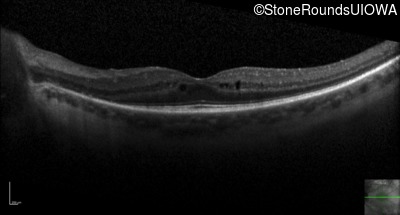

Optical Coherence Tomography - Right - 20/40 -1

Exemplar / OCT Stack